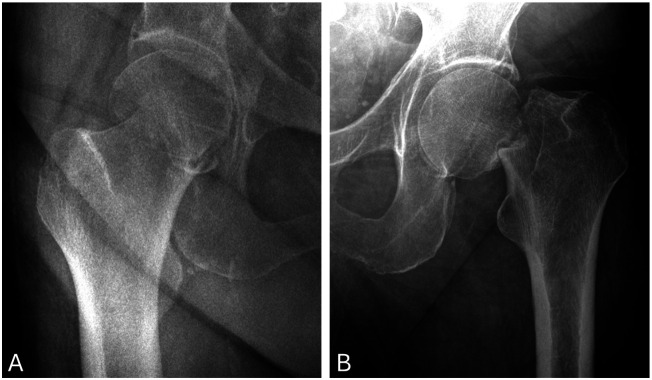

Results: The study included 193 patients with femoral neck fractures (mean age: 76.8 years, age range=60 - 98 years) and 257 with osteoarthritis (mean age: 60.4 years, age range= 23 - 88). After excluding 22 femoral neck fracture and 90 osteoarthritis patients, 36 patients in the fracture group and 18 in the osteoarthritis group had a history of malignancy, with 10 and 2 patients, respectively, having known metastases. Incidental metastatic bone disease was identified in four femoral neck fracture patients, while no neoplastic findings were detected in the osteoarthritis group.

Conclusion: Routine pathological examination of femoral heads is particularly relevant in femoral neck fracture cases, where the risk of detecting metastatic disease is higher. While thorough preoperative assessments and meticulous intraoperative evaluations aid diagnosis, the decision to submit specimens for pathology should be guided by the surgeon's clinical judgment and patient-specific factors.